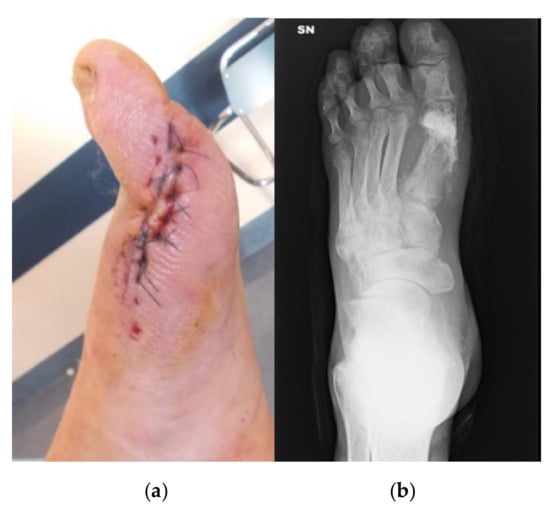

3.2. Metatarsal Lesions